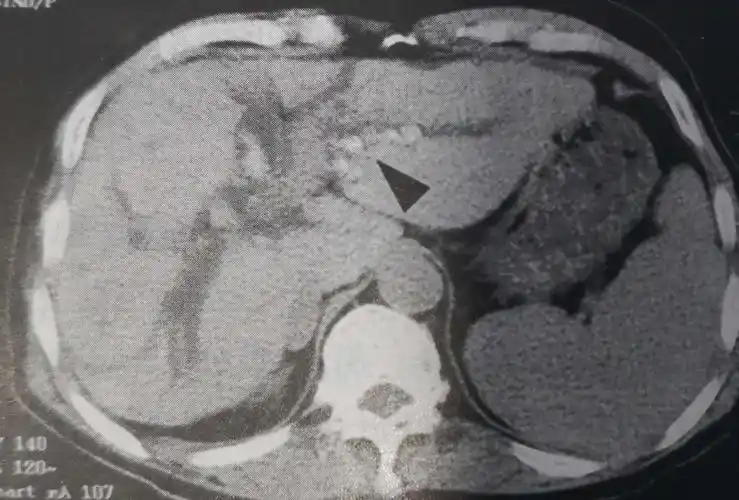

检查ct发现胆总管结石.

腹部ct可见明显胆总管扩张增粗,其内多发结石,肝内胆管也伴随扩张